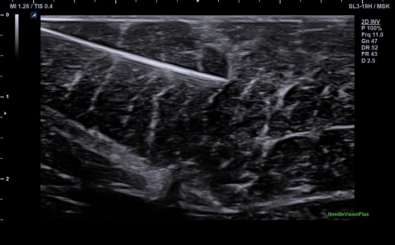

Needle Vision

CLINICAL IMAGES

臨床影像